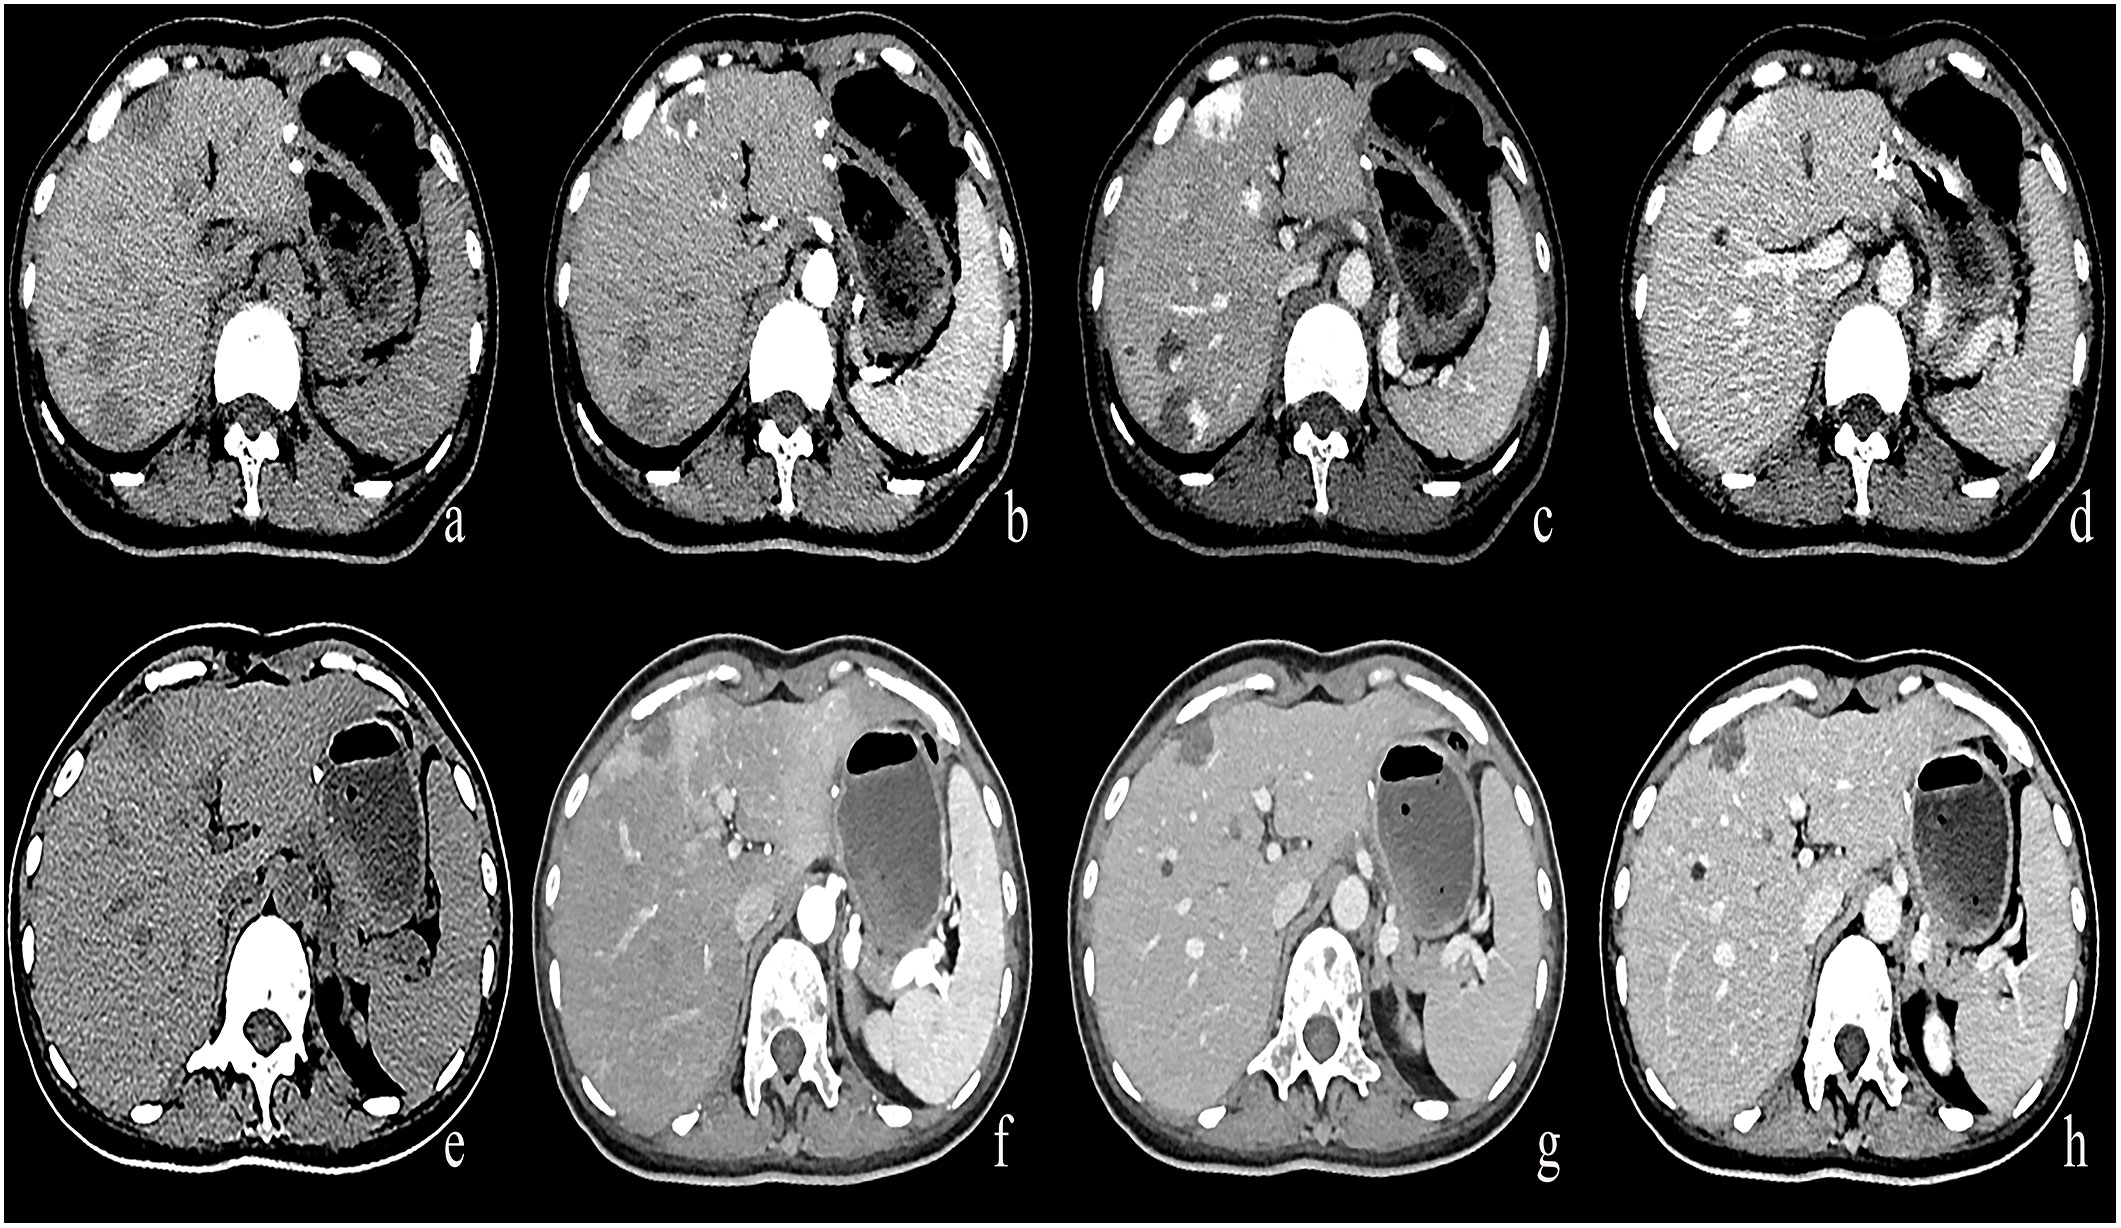

Figure 4 (A–D) A round low-density mass in the left inner lobe of the liver was shown in the plain CT. The lesions demonstrate peripheral nodular discontinuous enhancement in the arterial phase and centripetal filling in the portal and delayed phases. (E–H) After treatment with Bevacizumab, the lesions showed insignificant enhancement.

Figure 5 (A–D) A round low-density mass in the right lobe of the liver was shown in the plain CT. The lesions demonstrate peripheral nodular discontinuous enhancement in the arterial phase and centripetal filling in the portal and delayed phases. (E–H) After treatment with Bevacizumab, the lesions showed circular enhancement.